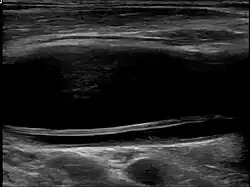

| Dissection in the carotid artery | |